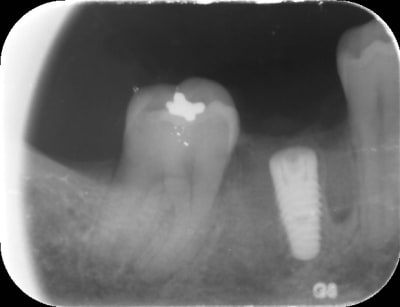

Exemple d'extraction implantation immédiate sans avoir fait de scanner :

Img 0816 dwoxje - Eugenol

Img 0817 kzosa4 - Eugenol